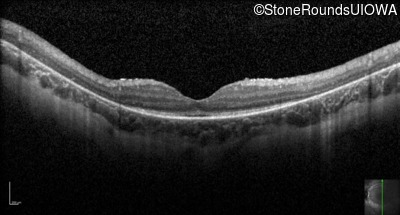

Optical Coherence Tomography - Right - 10/100 -1 sc

Exemplar / OCT Stack